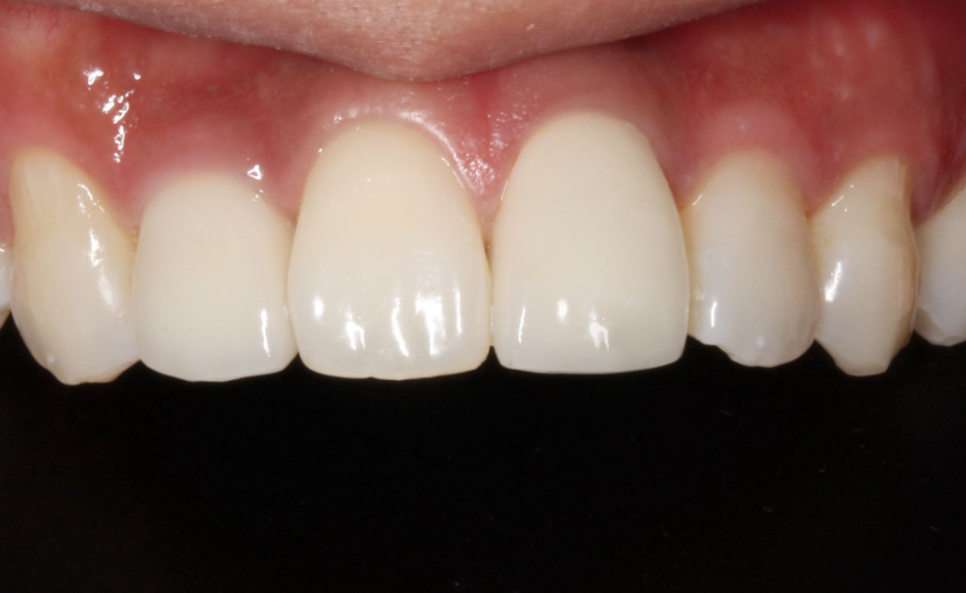

BEFORE

AFTER

앞니가 깨졌다면 꼼꼼한 상담을 통해서

그에 맞는 치료방법을 선택해야합니다.

앞니는 음식물을 절단하는 역할을 하고 얼굴의 정면에 위치한 치아인 앞니가 치아깨짐이 가장많이 발생하는데요. 치아가 깨진 경우에는 깨진 정도에 따라 치료방법이 달라지는데 깨짐이 작은 경우에는 비교적 간단히 치료가 가능하고 파손범위가 넓고 신경손상까지 의심된다면 엑스레이 촬영을 통해 치아 뿌리에 이상이 있는지 확인해야합니다.